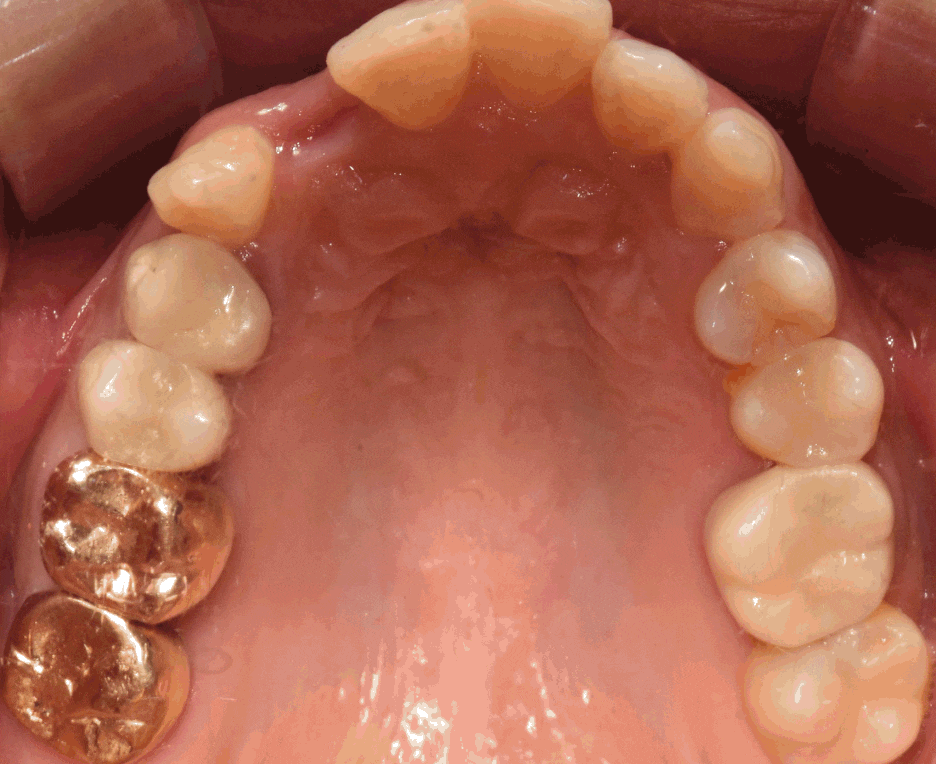

이제 최종 결과를 보여드리겠습니다.

이제, 흡잡을 곳이 없군요.

교정치료 및 발치와보존술, 임플란트 시술의

복합 결과를 보고 있으며 3년이라는 긴 기간이

소요되어서 원래의 구강 내 상태를 되찾아드렸네요.